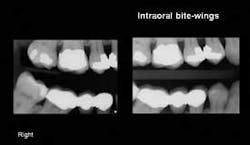

Intraoral bitewing radiographs (Figs. 3A and 3B): These radiographs, used for nearly a century, have allowed observation and diagnosis of initial dental caries in the past. However, with the advent of reduced radiation, bite-wing radiographs have decreased in value relative to showing initial caries. Additionally, when the currently available, relatively thick, sensor holders are used, they often open the mouth so far that the cervical areas of the teeth are not clearly visible on the radiograph. When using the intraoral bite- wings for patient education, the duplication of some teeth can be confusing to patients.

Extraoral bitewing radiographs (Fig. 4): This concept, currently available from PLANMECA USA and Sirona, shows the teeth, the periapical areas, and the related bony structures. These images are very educational for patients, and allow better diagnostic capability for practitioners than intraoral bitewings.